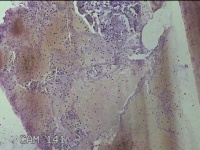

宫颈赘生物

性别

女

年龄

51岁

临床诊断

子宫多发性肌瘤 宫颈多发赘生物 宫颈息肉 子宫异常出血

一般病史

阴道断续流血数月余。

标本名称

大体所见

灰白暗红色肿物3x2.8x1.8cm一个,表面糜烂,切面灰白暗红色,质软。

图2